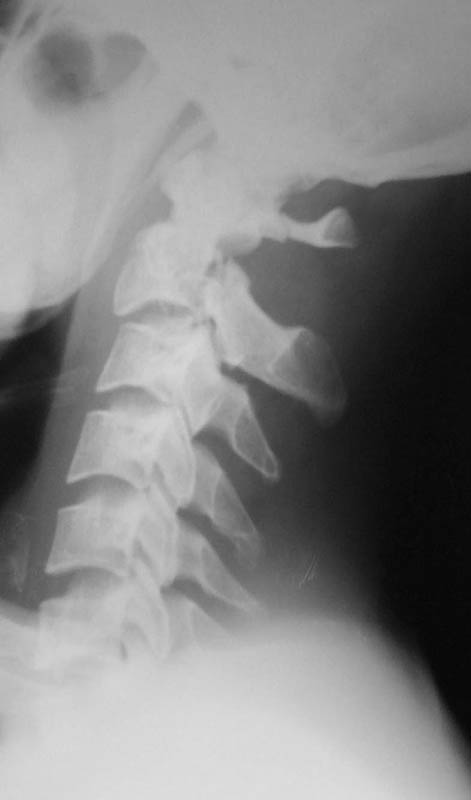

From: DR T I GEORGE

The cervical spine x-ray done on traction in neutral, extension and flexion. Images attached. Request comments.

txn extension

txn neutral

txn flexion

The skull traction is being continued. My colleague, Dr K P Ramkumar, Chief of our Spine unit, said that the the cervical injury belongs to Levine type II and most probably it will be conservative management only. However he wants to repeat the x-ray on traction after a few days and do also a dynamic flexion and extension view. The need for surgical intervention will be decided after this. He also feels that patient has a subjective numbness of finger tips and mild grip weakness. According to him this indicates that the spinal cord had minimal trauma.

I was disappointed that there was not even one comment after the cervical spine dynamic views were presented. Though there is instability, the CT picture showed that the body of C2 was totally comminuted and hence a decision to keep the patient in Halo was taken by my colleague in charge of the spine unit. After the consolidation of the body of C2 if required he will go through a formal C2-3 fusion.